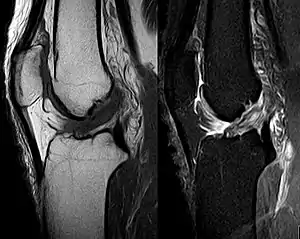

Though clinical examination in experienced hands can be accurate, the diagnosis is usually confirmed by magnetic resonance imaging, which provides images of the soft tissues like ligaments and cartilage around the knee.[1] It may also permit visualization of other structures which may have been coincidentally involved, such as the menisci or collateral ligaments.[30] An x-ray may be performed in addition to evaluate whether one of the bones in the knee joint was broken during the injury.[9]

MRI is perhaps the most used technique for diagnosing the state of the ACL, but it is not always the most reliable technique as the ACL can be obscured by blood that fills the joint after an injury.[31]